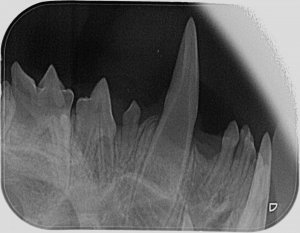

Ich hab zwar hier schon einige röntgenzahnbilder gesehen wo von Knochenabbau die rede war, deswegen hatte ich die Stellen markiert wo es (für mich ) auch so aussah, aber wahrscheinlich ist das in Ordnung so. Ich hoffe ja dass sich dazu noch jemand meldet und mir grünes Licht gibt.